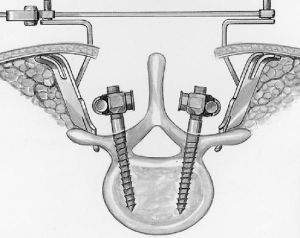

Хирургическое лечение спондилолистеза заключается в фиксации «разболтанных» позвонков титановыми винтами. Винты вводятся в позвонки через дужки позвонков (с лат. «педикули»), поэтому такая фиксация называется «транспедикулярной». Данный метод фиксации позвонков был впервые применен Roy-Camille в 1963г. и используется благодаря своей высокой эффективности по всему миру до настоящих дней.

Наиболее современным методом фиксации в настоящий момент является миниинвазивная технология введения винтов через небольшие разрезы. Этот метод позволяет меньше травмировать мышцы разгибатели позвоночника при введении винтов, а также более быстрому выздоровлению пациента и возвращению к обычному образу жизни, активному отдыху и работе. Технология данной фиксации заключается в использовании канюлированных винтов, т.е. винтов с отверстием в центре. В начале в тело позвонка вводится спица, а уже по спице вводится винт. Удаление грыжи диска и введение кейджа в межтеловой промежуток производится через тот же разрез, что и введение винтов.